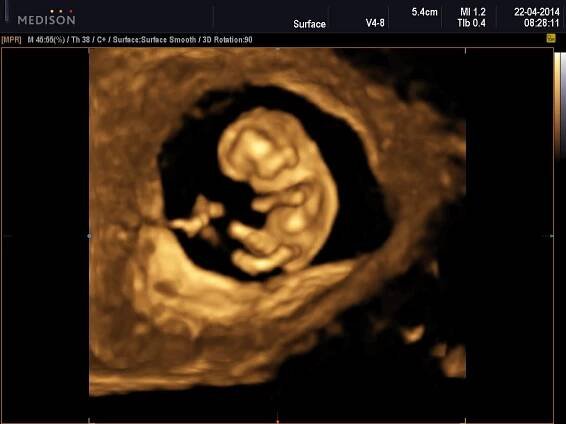

3D sonografia / 3D ultrazvuk - Prvý trimester - Celý plod

3D ultrazvuk je lékařská ultrazvuková technologie, často používaný v porodnické ultrasonografii (během těhotenství), poskytující troj-dimenzionální obrázek plodu. Wikipedie